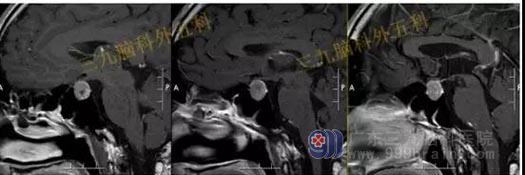

头部MR检查提示:垂体内示一团块状不均匀稍短T1稍短T2异常信号影,FLAIR序列呈稍高、等混杂信号,边界清晰,范围约为2.4×1.5×1.8cm,增强后强化不明显。视交叉受压稍上抬,垂体柄左偏,双侧颈内动脉未见受包绕。

手术过程:内镜下经鼻蝶垂体腺瘤切除术,术中磨除鞍底,有序切除肿瘤,质地硬,沿着肿瘤包膜全切肿瘤,垂体位于左侧,术中垂体保护完整,无海绵窦侵犯。

术后复查头部MR检查提示:原病灶已切除。